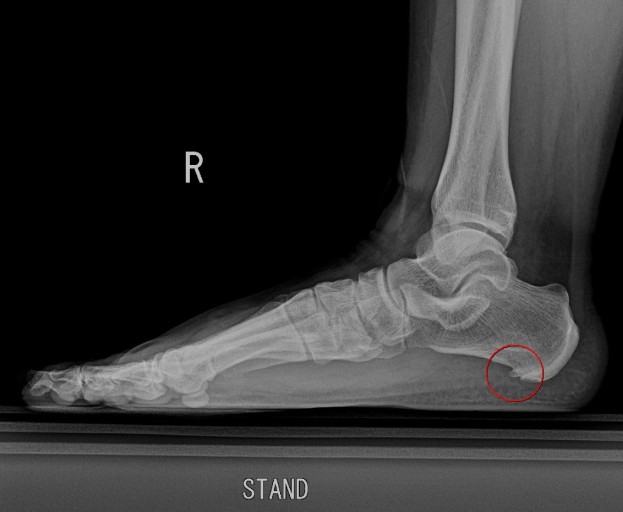

족저근막염의 원인

족저근막염은 우리 발바닥에 있는 족저근막 이라는 조직이 염증을 일으켜서 발생되는 병인데, 이 족저근막이 발바닥을 지탱하고 걸음걸이를 안정화 시키는 역할을 한다. 이 조직에 과도한 스트레스가 가해지면 염증이 생기고, 이게 바로 족저근막염이다.

주요 원인으로 과체중 , 잘못된 신발, 장시간 서있거나 걷기 등이 있는데, 나는 저 세가지에 모두 다 해당되었다 ㅜ 아무리 생각해봐도 발바닥이 너무 큰 과부하가 걸린게 원인인듯 하다